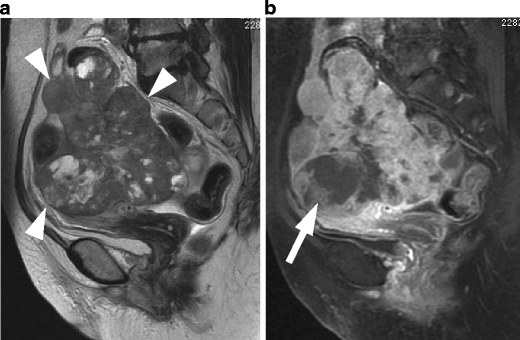

Leiomyosarcoma in a 60-year-old woman. a Sagittal T2-weighted image demonstrates an irregular-shaped large mass of heterogeneous intensity in the posterior wall of the uterus (arrows). b Postcontrast T1-weighted images with fat suppression demonstrate multifocal, unenhanced areas of necrosis within the tumor

Endometrial stromal sarcoma in a 47-year-old woman. a Sagittal T2-weighted image demonstrates an ill-defined lesion of slightly increased intensity in the posterior myometrium of the uterus (arrows). Note the bands of low signal intensity within the lesion, which represent preserved myometrial bundles amidst the infiltrating nests of tumors cells. b Fusion image with DWI onto T2-weighted image reveals increased signal corresponding to the infiltration tumor in the myometrium